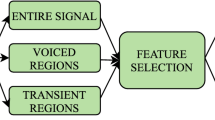

The full methodology of the study is concisely summarized in Fig. 1.